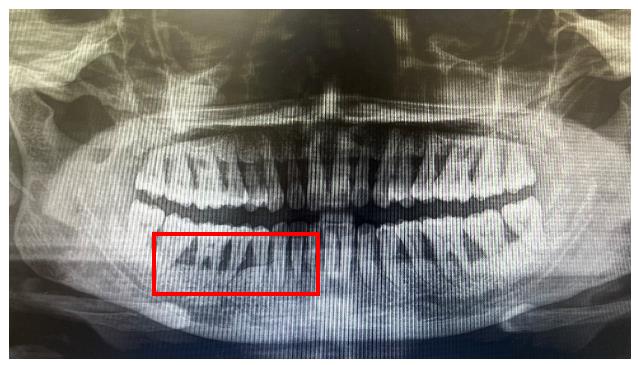

臨床表現(xiàn)變化:

輔助檢查: